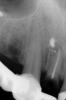

lavrikk Опубликовано 28 августа, 2012 Поделиться Опубликовано 28 августа, 2012 Со слов пациентки по поводу кисты 1.2 проведена резекция верхушки много лет назад. Зуб не беспокоил. Чем грозит изготовление ВКВ и затем одиночной коронки на этот зуб? Оправдано ли? Или имеющейся длины корня недостаточно для необходимого соотношения коронка-корень. В канале РФ. Направил бы на имплантацию, но не тянет. На ВЧ планируется изготовление м/к мостов 1.6-1.3 и 2.2-2.5 и одиночных коронок 1.1, 2.1, 2.6. А не знаю что делать с 1.2. Консоль или огромный мост делать не хочется. Буду рад любым советам. Ссылка на комментарий

lavrikk Опубликовано 28 августа, 2012 Автор Поделиться Опубликовано 28 августа, 2012 Раз уже начал тему здесь, то вопрос к коллегам-имплантологам. Возможна ли имплантация 1.2 без костной подготовки? На панораме неслабое разрежение кости. После удаления, кюретажа и выскабливания пломбировочного материала там останется что-нибудь? Ссылка на комментарий

IvanK Опубликовано 28 августа, 2012 Поделиться Опубликовано 28 августа, 2012 Судя по прицельнику - ничего сверхъестественного. В эстетически значимой зоне почти всегда что-то нужно, бывает достаточно пластики мягк тк Ссылка на комментарий